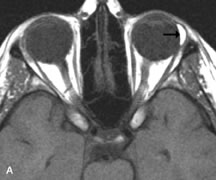

Metastatic Tumors

Breast carcinoma metastatic to the orbit has been demonstrated to be hypointense to the surrounding orbital fat on T1-weighted studies and hyperintense on T2-weighted images and has an affinity to the extraocular muscles (Fig. 20).50,64 The MRI characteristics of prostate carcinoma metastatic to the orbit have been described as involving the greater and lesser wing of the sphenoid, orbital roof, and optic canal. Diffuse bone hypertrophy with isointense or slightly hyperintense tissue on T1-weighted images represents the osteoblastic carcinomatous bone infiltration. Contrast enhancement is variable on T1-weighted and fat-suppressed images.65

Fig. 20. A. T1-weighted MR scan demonstrates nodular enlargement of both medial rectus muscles (arrows). B. T1-weighted fat-suppressed contrast-enhanced scan confirms the presence of small metnstatic deposits within the muscles (open arrows).